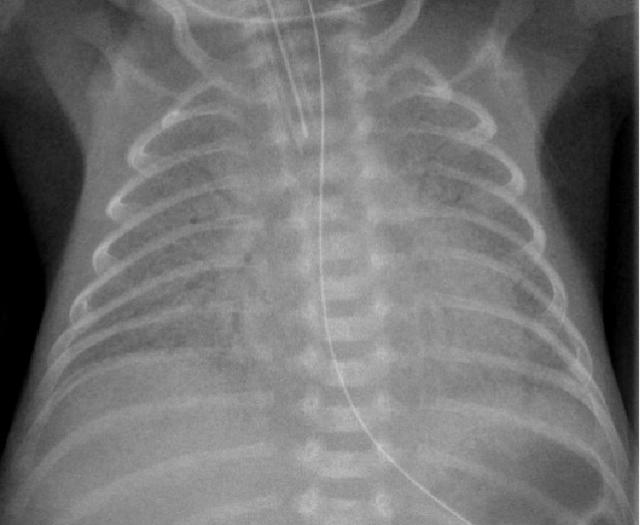

1、28周早产儿,呼吸困难1天。

可见双侧对称弥漫分布的的颗粒状高密度影。可见支气管充气。2、新生儿在剖腹产后数小时内出现呼吸困难。

仍可见双侧对称弥漫分布的的颗粒状高密度影,支气管充气征...